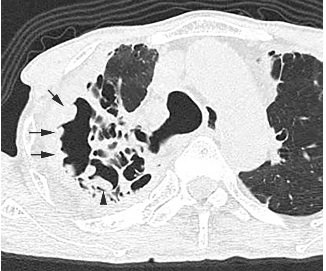

In patients with pulmonary aspergillosis, there is a high risk of haemorrhage. When this happens in the cavitary lesion, its wall shows lobulated thickening corresponding to fibrino-purulent material or to blood crust, therefore indicating a higher risk for haemoptysis. It may change quickly over a short period.

Article: The scab-like sign: A CT finding indicative of haemoptysis in patients with chronic pulmonary aspergillosis?